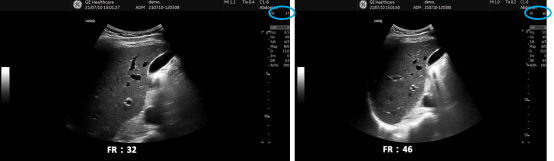

/ R+ {7 e, D& h3 ] 帧频(Frame Rate)

& T6 j) ^5 m- u j 较高的帧频可使瞬时分辨率最大化。操作者可通过降低图像的深度,减少聚焦点的数量,缩小扫描区域角度,降低扫描的线密度(彩色模式下也可以降低取样包数量)或使用预处理变焦来提高帧频。 1 ~2 d$ E9 C1 @& z' l